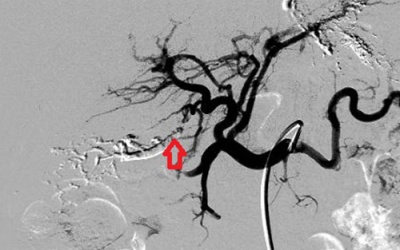

Xuất huyết tiêu hóa ồ ạt, người phụ nữ 60 tuổi ở Đăk Lăk vừa được xác định do mắc chứng rò mạch máu gan bẩm sinh, toàn thế giới chưa đến 100 ca.